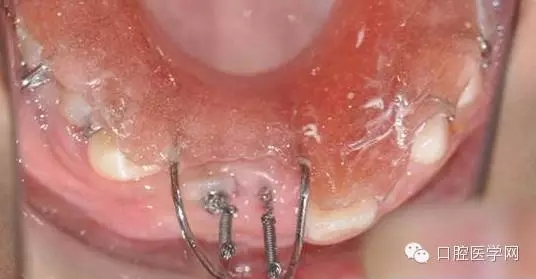

術(shù)前已經(jīng)給小孩取了牙模,所以就開始

“活動(dòng)可調(diào)、釣魚式牽引器”的制作。(后續(xù)的博客會(huì)詳細(xì)的給大家講一下制作要領(lǐng),和各種卡環(huán)變異的彎制。簡(jiǎn)簡(jiǎn)單單的彎制卡環(huán)可以完勝各種焊接或鑄造。 )

35.webp.jpg

36.webp.jpg

帶入口內(nèi)調(diào)整吊桿方向加輕力:

(咬合調(diào)整好,加輕力激活)